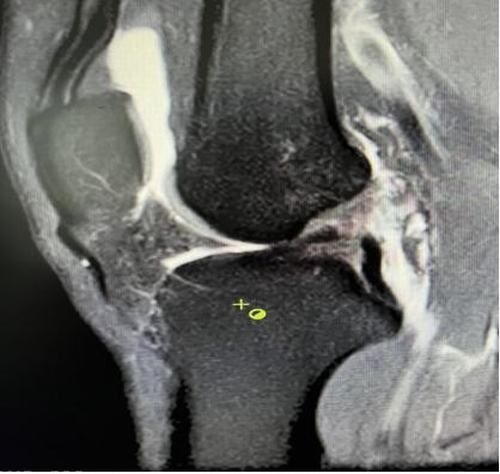

膝關節(jié)韌帶損傷磁共振

我院骨科三病區(qū)近期收治了4名膝關節(jié)交叉韌帶損傷患者。25歲的齊先生,因打籃球時不慎扭傷左膝,致右膝腫痛,遂來我院治療;30歲趙先生酷愛足球,扭傷右膝關節(jié)來我院就診;50歲的張先生、42歲劉先生因騎車滑倒摔傷、膝關節(jié)腫痛不適、活動受限,收治入院。骨科三病區(qū)李鵬主任團隊詳細查體以及完善影像學檢查后進行診斷:幾位患者共同診斷均有“前交叉韌帶損傷”,不同程度合并有“半月板損傷”、“股骨軟骨損傷”、“內(nèi)側副韌帶斷裂”。

經(jīng)患者同意后,李鵬主任手術團隊制定詳細手術方案。手術如期進行,經(jīng)團隊密切配合,對幾位患者分別順利完成關節(jié)鏡下膝關節(jié)鏡鏡檢、關節(jié)清理、股薄肌半腱肌取腱移植術、前交叉韌帶重建術、軟骨損傷微骨折術、半月板縫合修整術等。